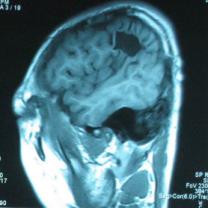

头颅CT和MRI可见颅骨缺损区下方软脑膜囊肿、脑软化灶或脑室穿通畸形(图2)。

图2:①和②CT及骨窗相显示右顶部颅骨缺损,其下方脑组织呈低密度改变;③-⑥MRI右顶局部颅骨缺如,脑组织轻度向外膨隆,右顶叶侧脑室体部旁局部脑组织缺如,代之以囊性长T1、长T2信号。